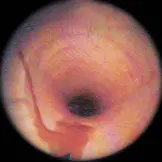

Gastroskopie (Magenspiegelung)

Mit Hilfe der Gastroskopie ist es möglich das Innere der Speiseröhre (Ösophagus) und des Magens (Gaster) anzusehen. Das Pferd sollte vor der Untersuchung mindestens 15 Stunden kein Futter aufgenommen und ungefähr vier Stunden kein Wasser getrunken haben. Nach dieser Zeit sollte der Magen sich physiologisch entleert haben und die gesamte Schleimhaut des Magens ist einsehbar. Das Endoskop wird am sedierten Pferd über den Nasengang in den Rachenraum vorgeschoben. Über die Speiseröhre gelangt man dann zum Magen und den Anfangsbereich des Dünndarms (Duodenum). Klinische Symptome bei Magengeschwüren können unter anderem Fressunlust, schlechter Ernährungszustand, Unrittigkeit und verminderte Leistuntgsfähigkeit sein.